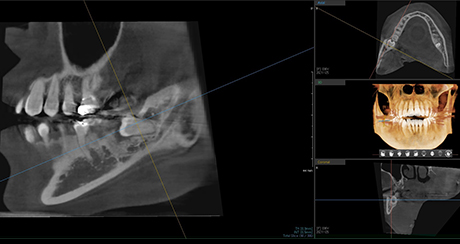

POINT

Extraction technique with nerve considerations

Using 3D CT, we evaluate the shape of the wisdom tooth, its roots, and surrounding nerves to support a safer extraction process.